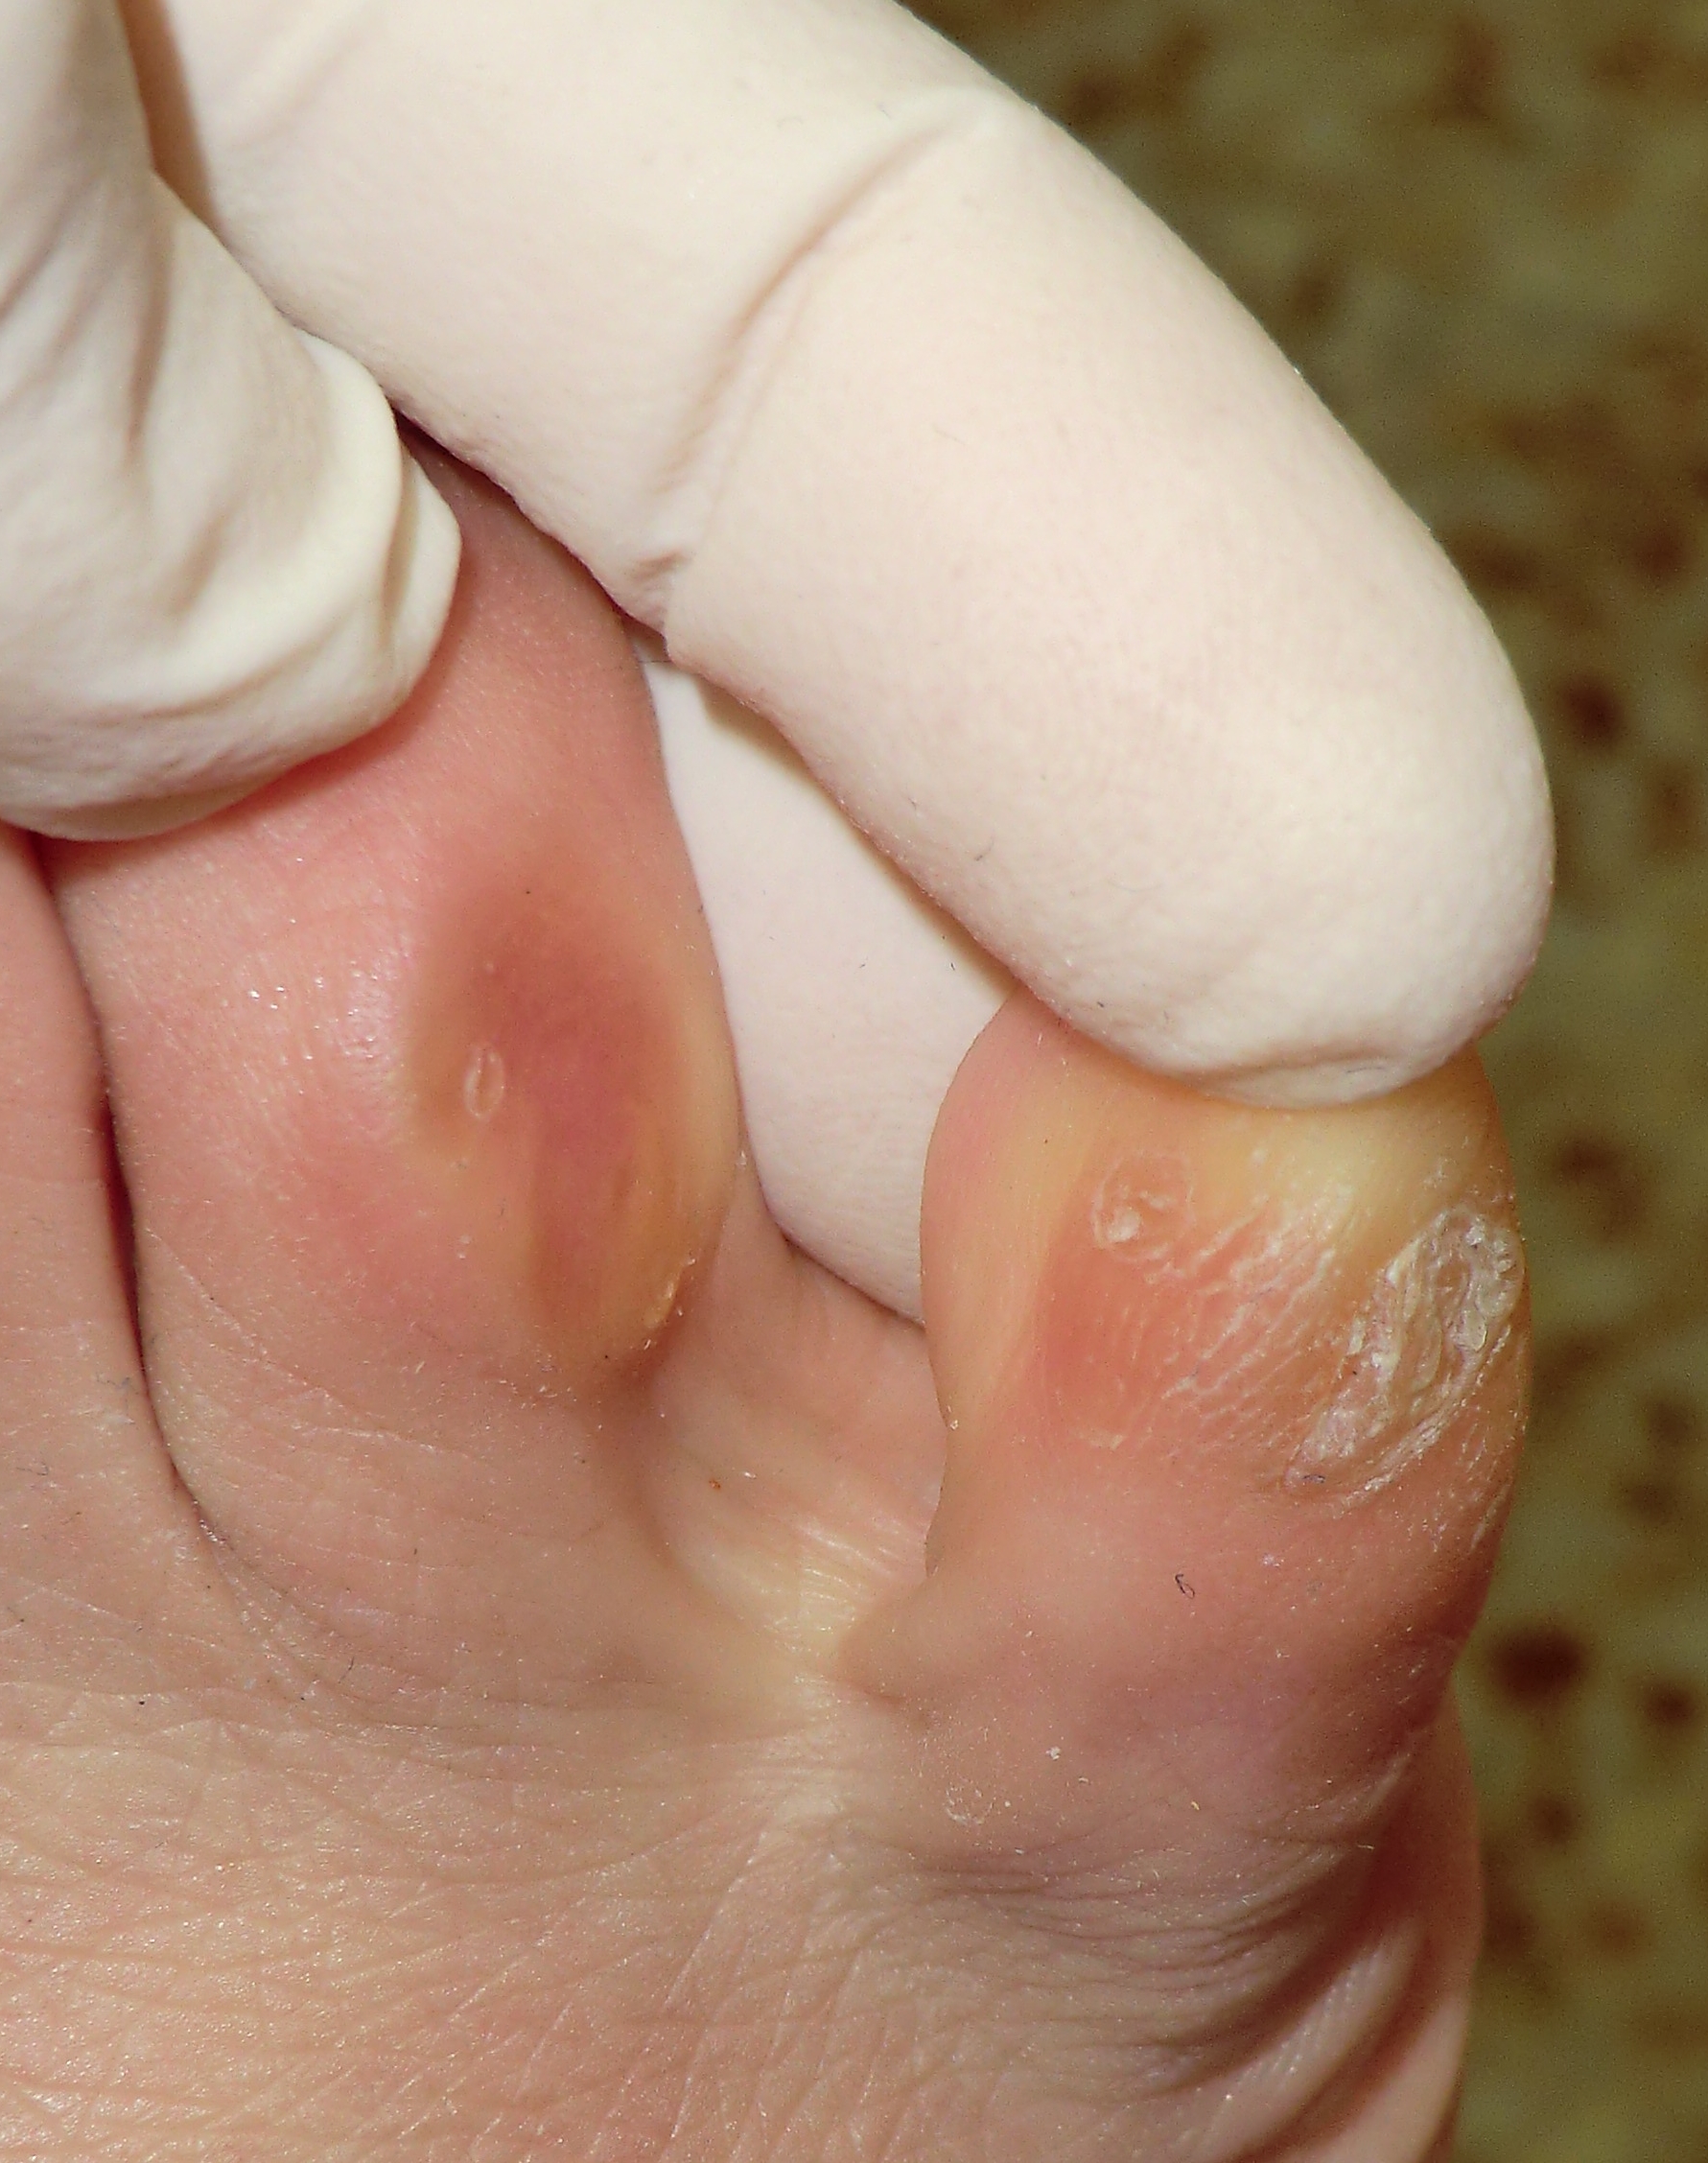

Los molestos y dolorosos «ojos de gallo» que suelen aparecer en los pies entre los dedos y/o encima de los mismos tiene solución definitiva y consiste en realizar una microcirugía local para el pulido del hueso que está generando dicha patología en la piel. Lo que ocurre generalmente es que la forma picuda que tienen las falanges (huesos de los dedos), generan junto con la rotación de algún dedo implicado y el calzado estrecho una presión constante en la zona y ello da lugar a un endurecimiento de la piel que finalmente se convierte en un callo circular siendo muy doloroso en ciertas zonas debido a la opresión que soporta.

En un principio el dolor puede cesar limpiando bien la zona y eliminando ese «callo» que genera el dolor pero éste vuelve a aparecer al poco tiempo de ser quitado porque el mecanismo que lo provoca está en el interior y no en el exterior donde se presenta. Por ello, para dar solución definitiva a ese «ojo de gallo» hay que trabajar desde el interior abordando el hueso implicado en el proceso.

La intervención es muy corta y sencilla, bajo anestesia local de la zona a intervenir y mediante cortes milimétricos podemos acceder a la zona picuda del hueso implicado y pulirlo eliminando así el pico óseo que genera presión sobre la piel afectada. Al tratarse de microcirugía no requiere de puntos de sutura en piel, el sangrado es mínimo y la recuperación inmediata.

Con este pequeño procedimiento aseguramos la desaparición definitiva del «ojo de gallo» ya que se deja el hueso totalmente romo para que no provoque ese efecto punzante que provoca la alteración en la piel.